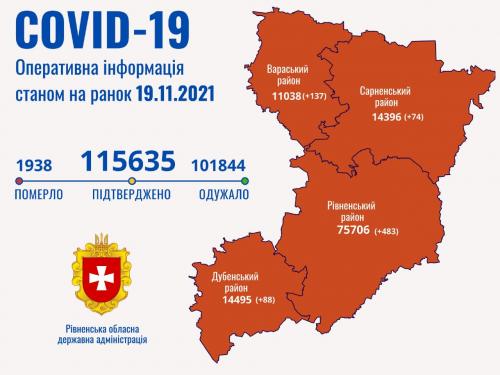

19.11.2021 11:08

Пів тисячі - у важкому стані, 9 жителів Рівненщини померли за добу від коронавірусу